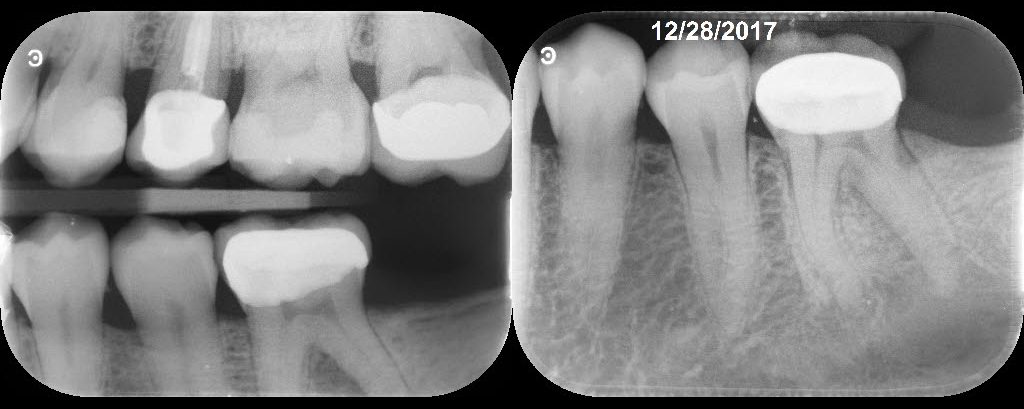

50 yof Necrotic Pulp. Symptomatic AP. 3 visits due to persistent drainage from the DL at the second visit two weeks later. Let the tooth sit in calcium hydroxide over one month before completing. Tooth was asymptomatic and dry canals at the third visit. Asymptomatic and functional at F/U.